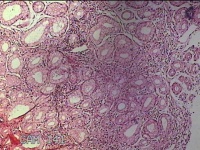

胃角粘膜

性别

男

年龄

29岁

临床诊断

复合性溃疡;慢性胃炎

一般病史

上腹部疼痛1个月余。

标本名称

大体所见

图2

良性病变。